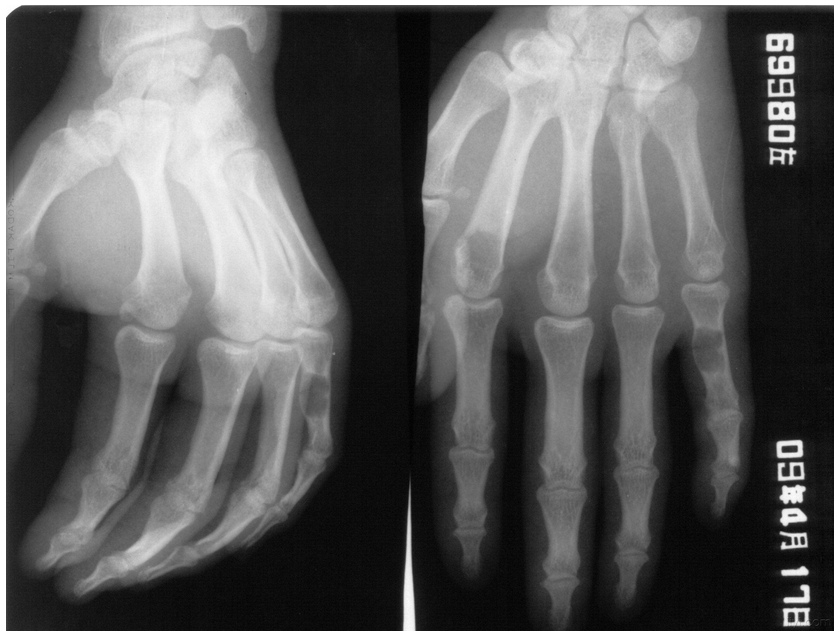

江西省医学科学院附属嘉佑曙光骨科医院的医师介绍:骨外伤线可呈横行、斜形、螺旋形等。骨外伤的形态不同,稳定性也不同。无移位骨折、嵌插骨折及横形骨折复位后不容易再移位,为稳定性骨折。斜形骨折、螺旋形骨外伤及粉碎性骨折不容易固定,为不稳定骨折。